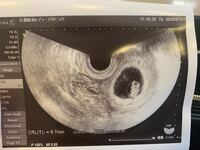

Oct 16, · 妊娠6~7週 胎嚢(gs)が少し大きくなり、胎芽・卵黄嚢を確認することが出来ます。 妊娠8~11週 胎芽から胎児へと進化する時期です。エコー写真では手や足を確認することが出来るようになります。健診時には胎児の頭殿長(crl)を計測し、成長を確認します。Sep 24, · 妊娠21週目の4dエコー写真 ちょっとわかりにくいかもしれませんがこちらを見ている画像です。 顔が少しだけ斜めになっていて、鼻、ほほ、口、手までリアルに写っていて驚きましたねNov 29, · エコー写真で性別判定出来る方いらっしゃいましたらお願いします!出生前診断で女児との結果が出たのにも関わらず、17週目のエコーでもっこりしたものが写りました。周りから男の子だね。と言われて混乱しています。実際、出生前診断の結

Jan 19, 21 · 妊娠7週6日(妊娠2ヶ月)のエコー写真 妊娠7週6日のエコー検査ではキユーピー人形のような形の胎芽が確認できました。 胎芽の頭からお尻までの長さである「頭殿長(とうでんちょう)」(CRL)は151mmで、推定週数は妊娠8週0日。妊娠7週のエコーの見方!心拍弱い・胎芽が小さく highclass 妊娠7週のエコーの見方のポイント 妊娠7週のエコー写真では、胎嚢(黒く塗りつぶされたような、胎芽を包む袋)と、その中に胎芽(白っぽい塊)が見られます。Mar 09, 14 · エコー写真の見方について、教えてください。本日5w2d、5週目入る手前に、家庭で妊娠検査薬で陽性を確認しました。昨日産婦人科へ行き経膣エコーにて、胎嚢らしきものを確認しました。先生によると、この時期にしては小さすぎるので、ま

妊娠7週2日目のエコー写真 心拍確認 Crlは13 3ミリ 2頭身になりました 保育士うたのブログ